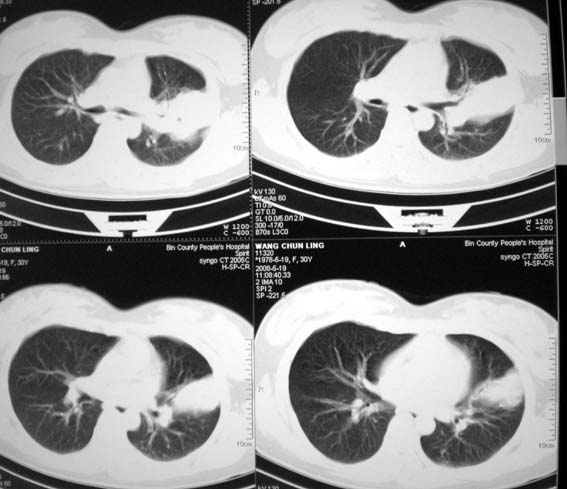

女,30岁,怀孕后3个月,拍片时肺结核,抗结核治疗4个月复查。

既然抗结核治疗4个月,一定做了结核相关检查,建议与原片比较看治疗效果,也可结合纤支镜取病理检查。

前段支气管通畅,但尖后段支气管闭塞,建议支纤镜除外肺癌,有原片吗,对比一下了。

结核.前段支气管通畅,但尖后段支气管闭塞,建议支纤镜除外肺癌